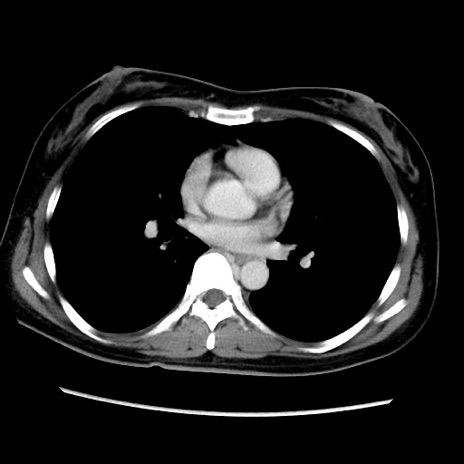

症例39(横断像)

【症例】40歳代女性

【主訴】上下腹部痛

【現病歴】2日目から下腹部痛あり。夜間は痛みで眠れなかった。昨日より上腹部痛と下痢が出現。臥位で痛みは軽快したため、休んでいた。本日になって臥位でも立位でも痛みが強くなってきたため救急要請。

【既往歴】子宮内膜症

【身体所見】部:平坦・軟、左上下腹部に圧痛あり、反跳痛あり。

【データ】WBC 21800、CRP 26.78